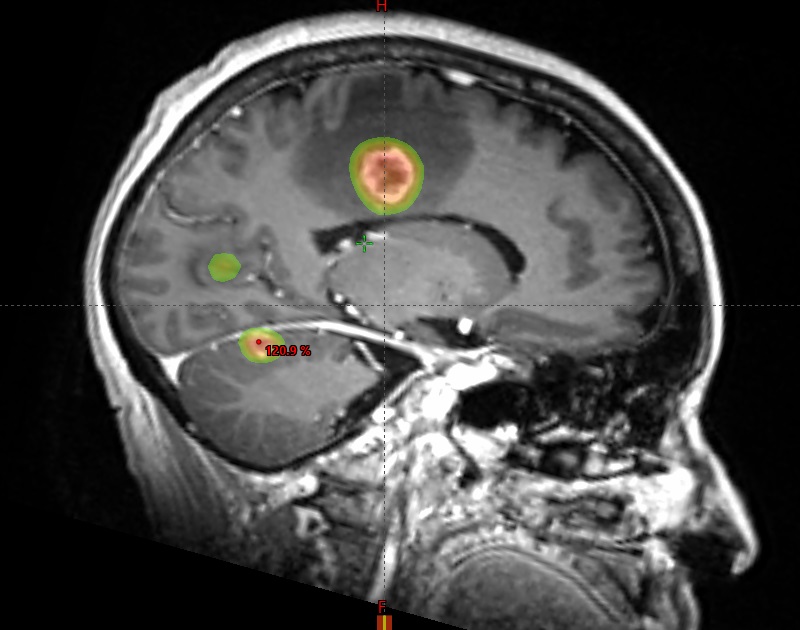

Images showing the Stereotactic Radiation Therapy plan which precisely targets several tumors in the brain with sparing of the normal brain.

SRS therapy is a minimally invasive surgical intervention that makes use of advanced 3D imaging to deliver highly focused beams of radiation to a specific target, such as a tumor.

Using SRS, Dr. Yeh and his team designed a treatment plan delivering focused, high-dose radiation to each lesion while sparing the surrounding healthy brain tissue.